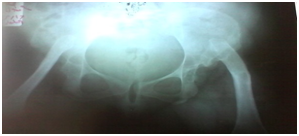

Her labs were normal apart from hyperglycemia, dyslipidemia & microalbuminuria. TSH was normal while FSH & LH were high for correlating phase indicating pre mature ovarian failure. Protein electrophoresis showed increase in alpha 2 globulin region. Abdominal & pelvic sonography revealed marked abdominal distension with multiple ovarian cysts indicating polycystic ovaries (PCO). Skeletal x- ray survey demonstrated bilateral hip dislocation with proximal femoral head & neck deficiency with shallow acetabulum (type III) (Figure 3). Echocardiography & CT abdomen were normal.

Figure 3 Echocardiography & CT abdomen were normal.